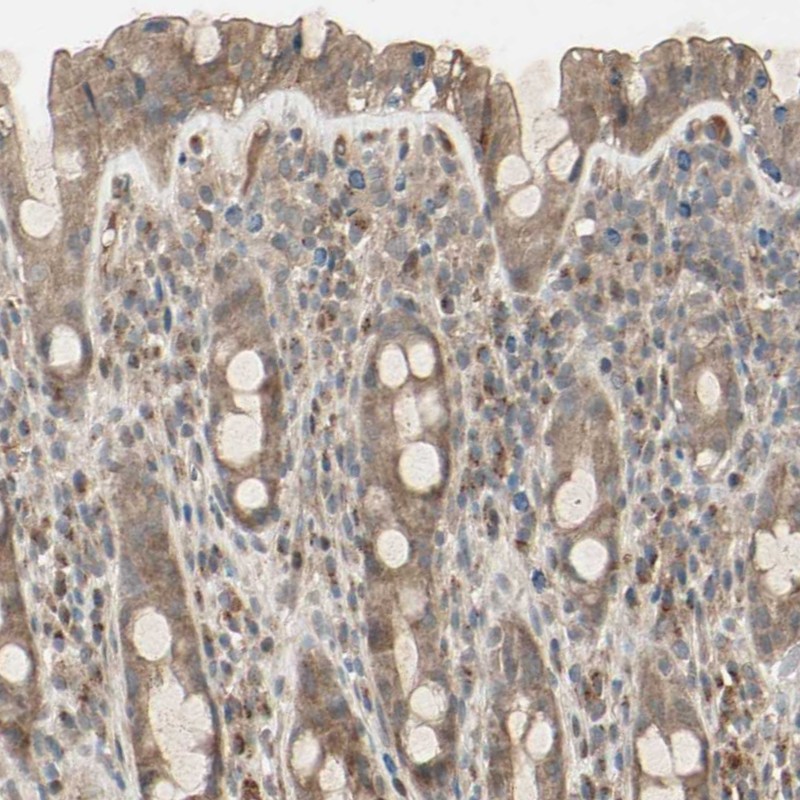

Immunohistochemical staining of human rectum shows moderate cytoplasmic positivity in glandular cells.